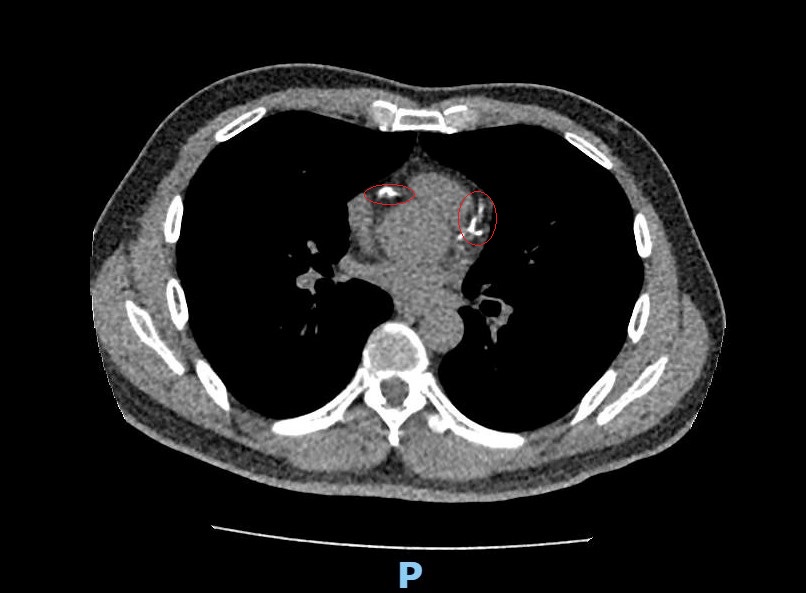

李學林指出,林先生原本僅做 LDCT 篩檢肺癌,卻意外發現血管鈣化;再進一步進行冠狀動脈電腦斷層檢查(CCTA),才確認三條血管內鈣化狹窄達 85%以上。李學林表示:「若延誤治療,林先生隨時可能發生急性心肌梗塞,情況相當危險。」

林先生本身有三高、家族史及吸菸習慣,屬典型心血管高風險族群,雖未發生急性心肌梗塞,但血管阻塞已悄悄累積。李學林表示,這次肺癌篩檢發現心血管鈣化,可說是「意外的及時預警」。

李學林提醒,觀察心血管鈣化可透過冠狀動脈電腦斷層檢查(CCTA),快速且無侵入性,但費用較高。若先做 LDCT,除了肺癌篩檢,也可掌握心血管鈣化情況,是健檢附加價值。